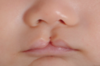

cleft lip (bilateral)